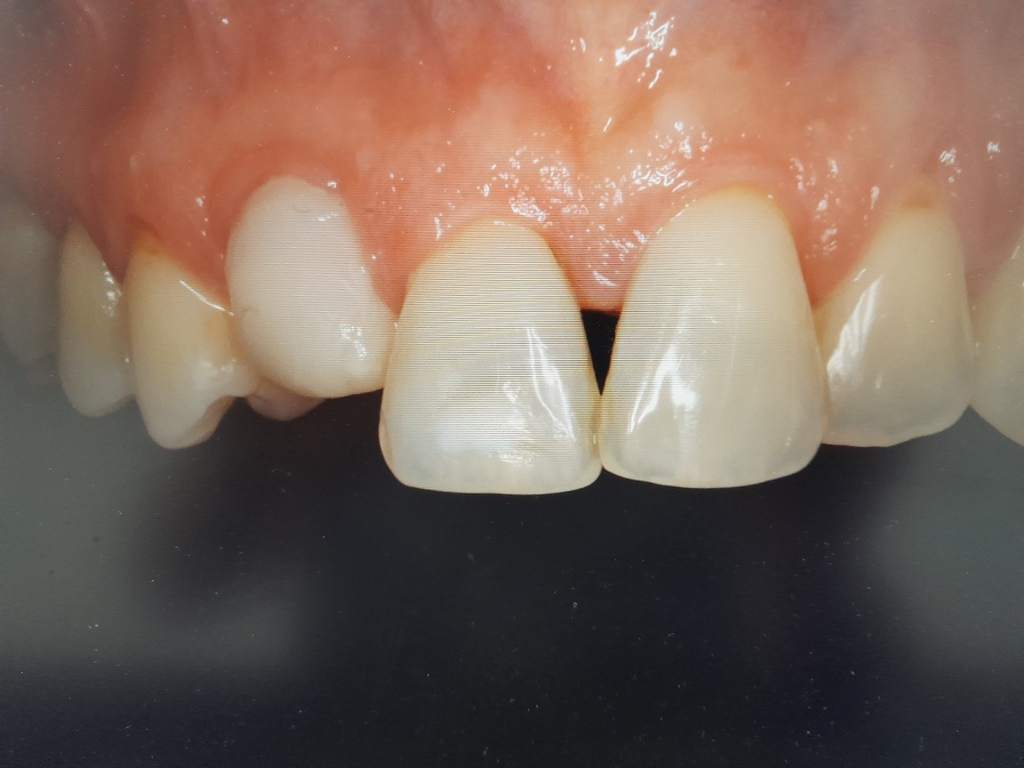

Αρχική εικόνα δοντιού

Τελική εικόνα δοντιού μετά από θεραπεία

4. ΠΡΟΣΘΕΤΙΚΗ ΑΠΟΚΑΤΑΣΤΑΣΗ ΔΟΝΤΙΩΝ

Σε δόντια στα οποία έχουμε μεγάλη απώλεια της οδοντικής ουσίας τους, η προσθετική τους αποκατάσταση έχει καθοριστική σημασία για τη μακροχρόνια διατήρησή τους. Προσθετικές προσεγγίσεις με ανασυστάσεις ρητινών σε συνδυασμό με ίνες Ribbond, ένθετα-επένθετα, θήκες μεταλλοκεραμικές, θήκες ζιρκονίου ολικής μορφολογίας ή ζιρκονίου με κεραμική επικάλυψη, προστατεύουν τις οδοντικές δομές και αποκαθιστούν τη λειτουργικότητα και την αισθητική.

Οι προσθετικές εργασίες τόσο επί των δοντιών όσο και επί των εμφυτευμάτων , κατασκευάζονται στο σύγχρονο οδοντοτεχνικό εργαστήριου του κ. Χατζηττοφή Θεοδόση, όπου με τη χρήση των πιο προηγμένων τεχνολογιών εξασφαλίζεται η άριστη εφαρμογή, η αντοχή και η αισθητική των αποκαταστάσεων.